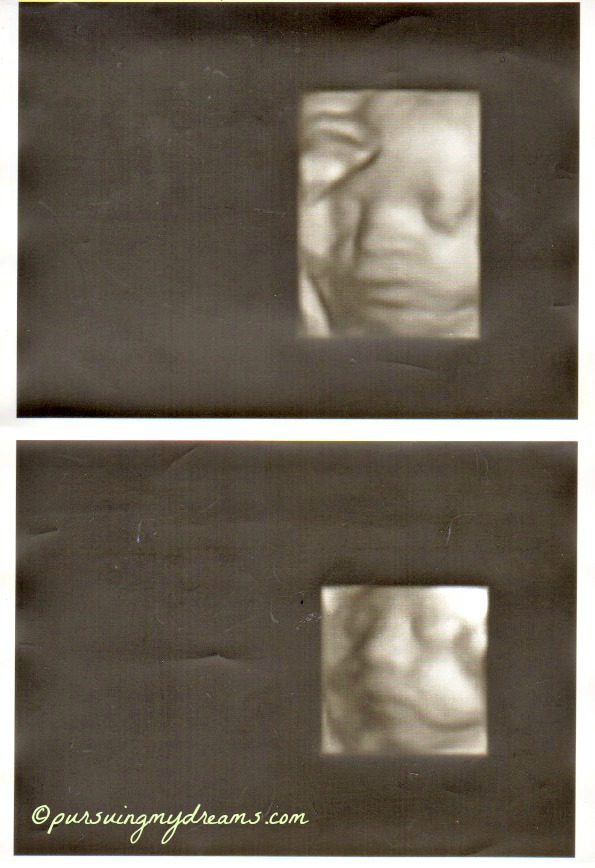

Sebagai penutup saya sertakan foto hasil usg anakku. Ini usg saat usia kehamilan 25 minggu. Dilakukan di kliknik Mannheim. Setelah itu sampai saat ini dokter tidak pernah melakukan pemeriksaan usg lagi karena semuanya baik-baik saja. Jadi hanya diperiksa posisi kandungan.

Iya bang keliatan jelas, padahal itu masih 25 minggu. Ga tau saya usg apa namanya hehehe.

Hidung anakku ngikut aku Ndang alias pesek, dokternya bilang gitu 😆 .